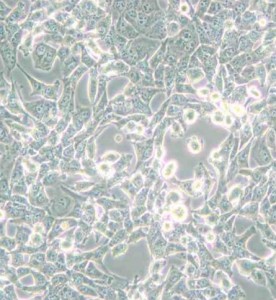

95-D[PLA-801D]人高轉移肺癌細胞

中文名稱 :人高轉移肺癌細胞

細胞簡稱 :95-D [PLA -801D ]

細胞別稱 :PLA 801D; PLA 801-95D; 95D; 95-D; 801-D

細胞形態 :上皮細胞樣

生長特性 :貼壁細胞

95-D 細胞是一株高轉移肺癌細胞。

組織來源 :肺癌

細胞類型 :腫瘤細胞

腫瘤類型 :肺癌細胞